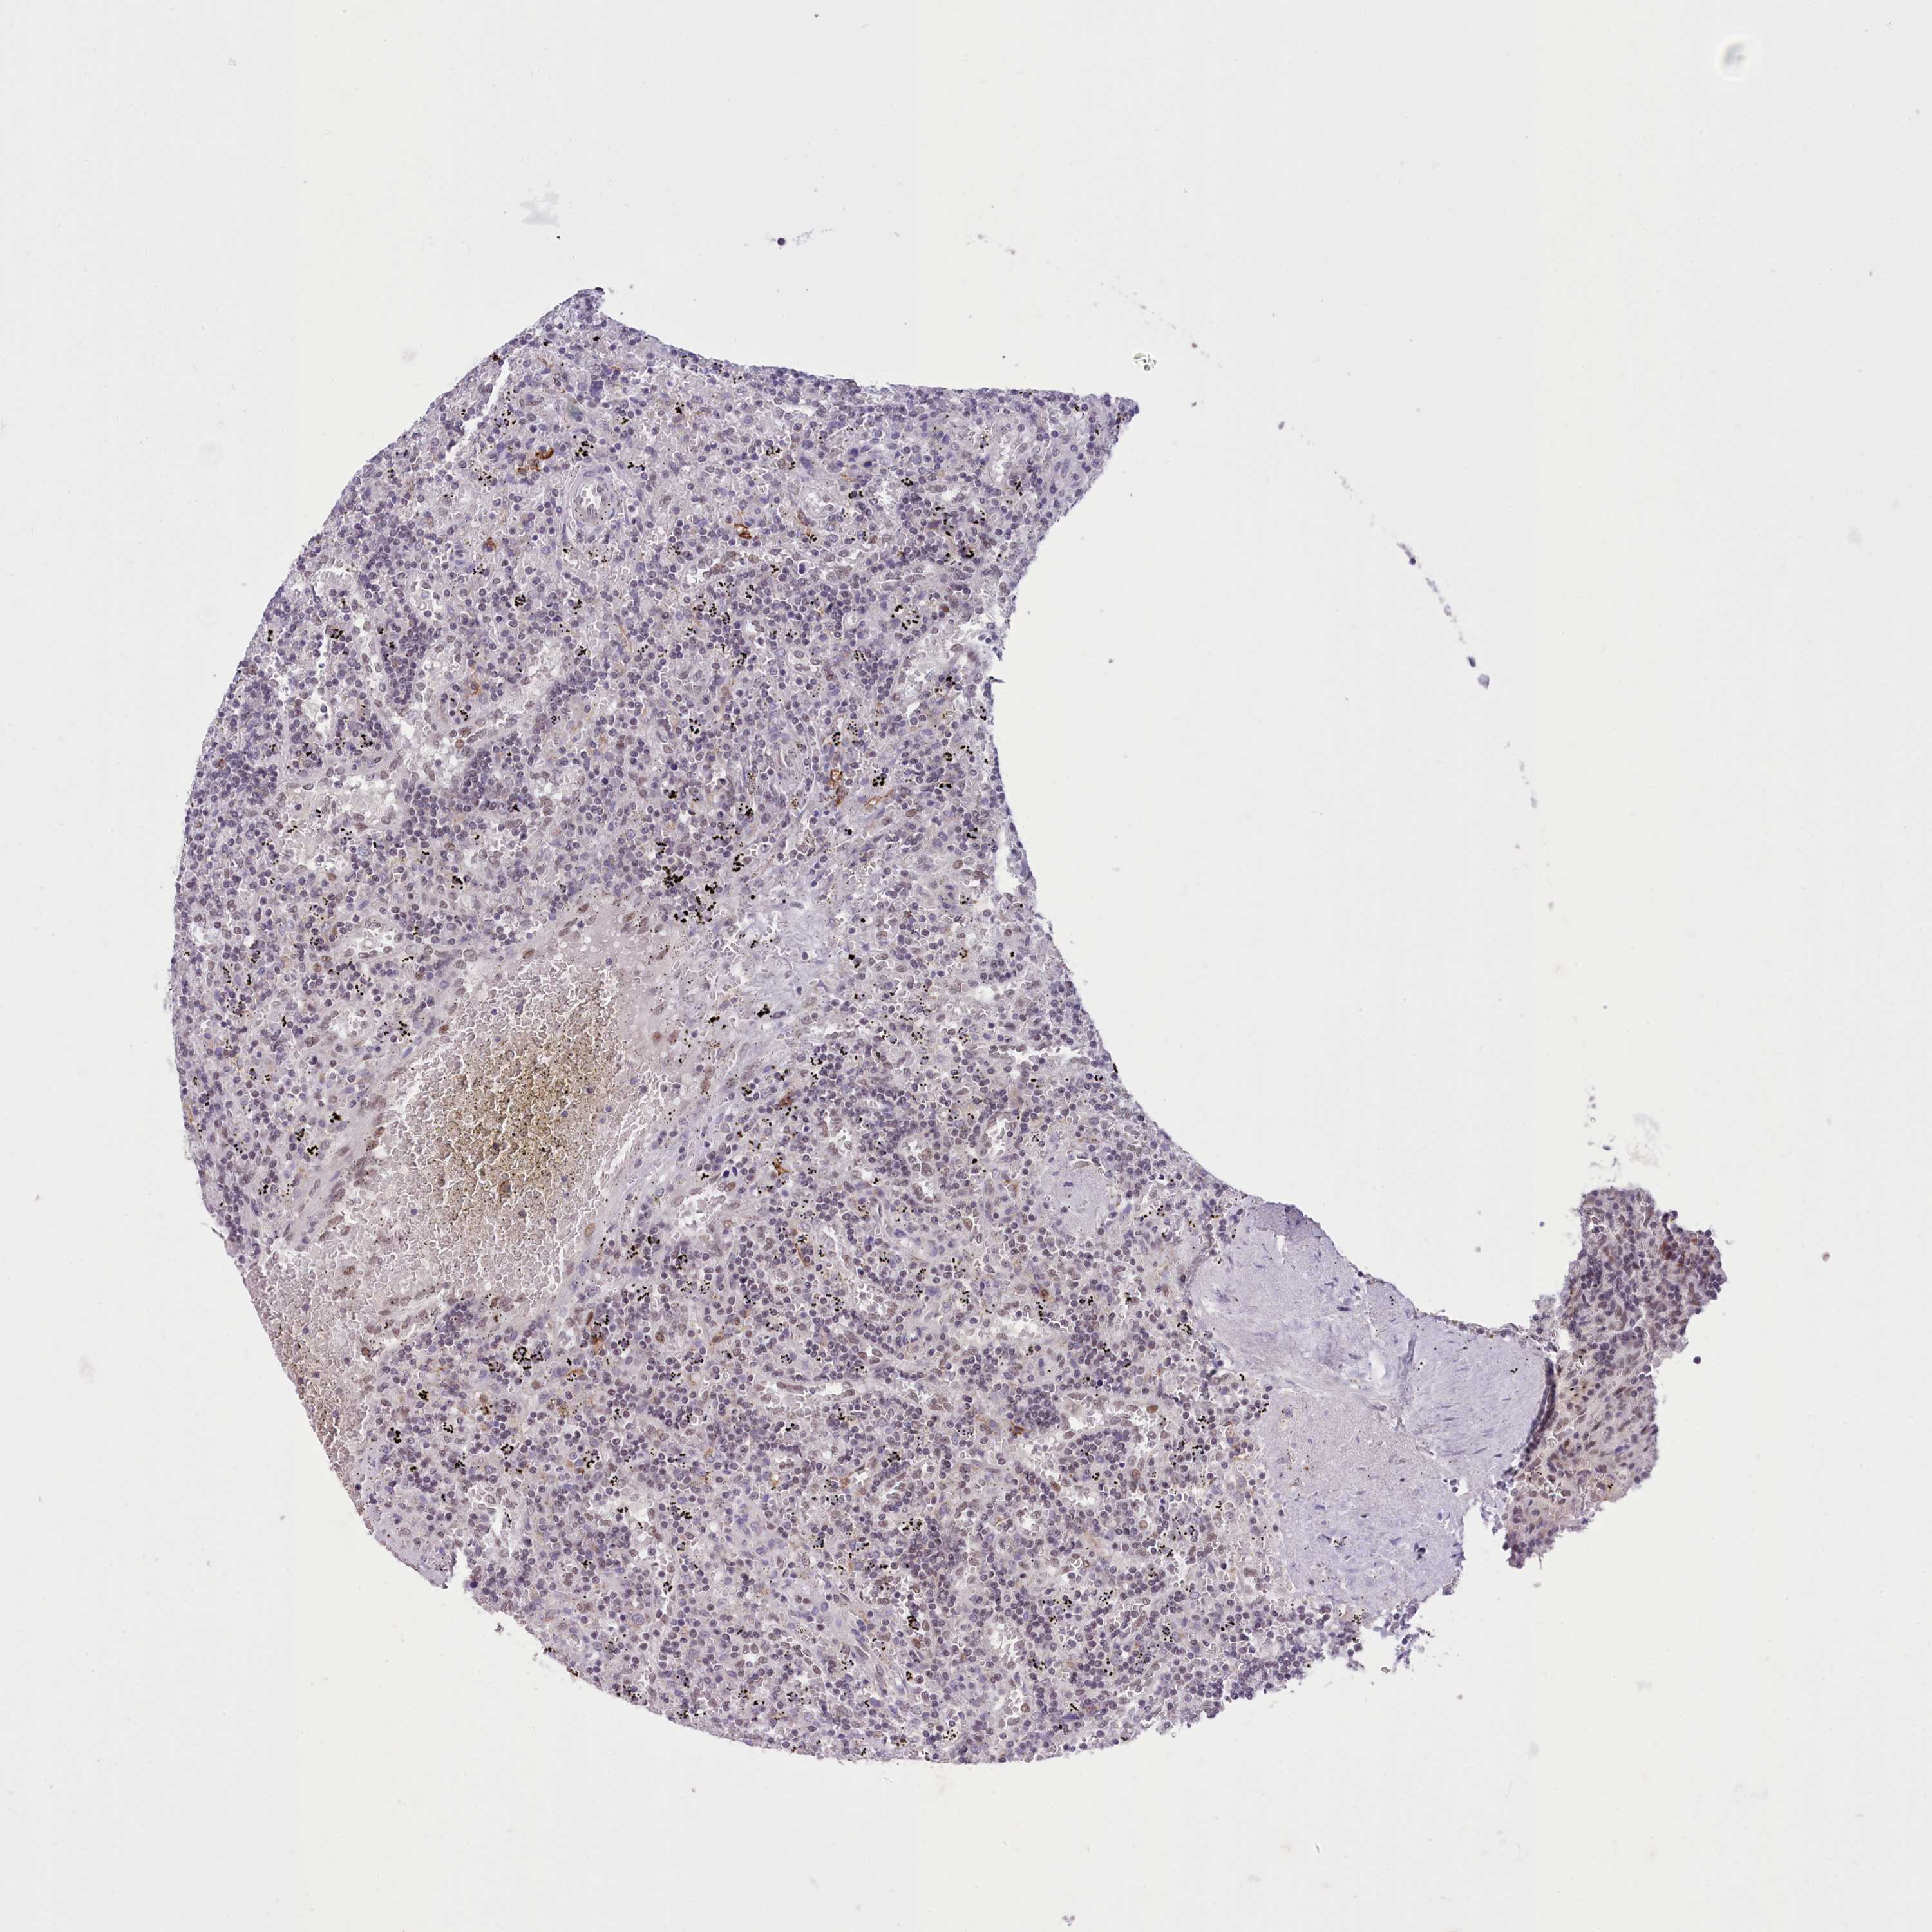

CANCER LYMPHOMA Show tissue menu

LYMPHOMA - Protein expressioni

A mouse-over function shows sample information and annotation data. Click on an image to view it in a full screen mode. Samples can be filtered based on level of antibody staining by selecting one or several of the following categories: high, medium, low and not detected. The assay and annotation is described here.

Each image is clickable and will lead to virtual microscopy that enables deeper exploration of all samples and also displays staining intensity scores, fraction scores and subcellular localization as well as patient and tissue information for each sample.

Antibody HPA048722

Staining

High

Medium

Low

Not detected

Intensity

Strong

Moderate

Weak

Negative

Quantity

>75%

75%-25%

<25%

None

Location

Nuclear

Cytoplasmic/membranous

Cytoplasmic/membranous,nuclear

Hodgkin's disease, NOS

Malignant lymphoma, non-Hodgkin's type, High grade

Malignant lymphoma, non-Hodgkin's type, Low grade